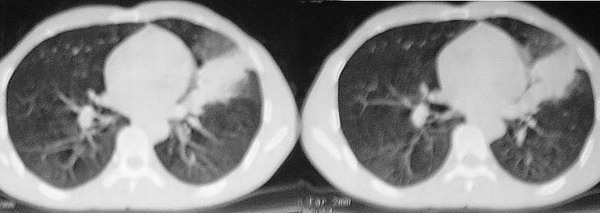

2.)纵膈窗片见:垂直胸膜边缘平直甚至微凹;

4).实变灶内密度失均,有少量短管状气影,可能为合并之支扩.